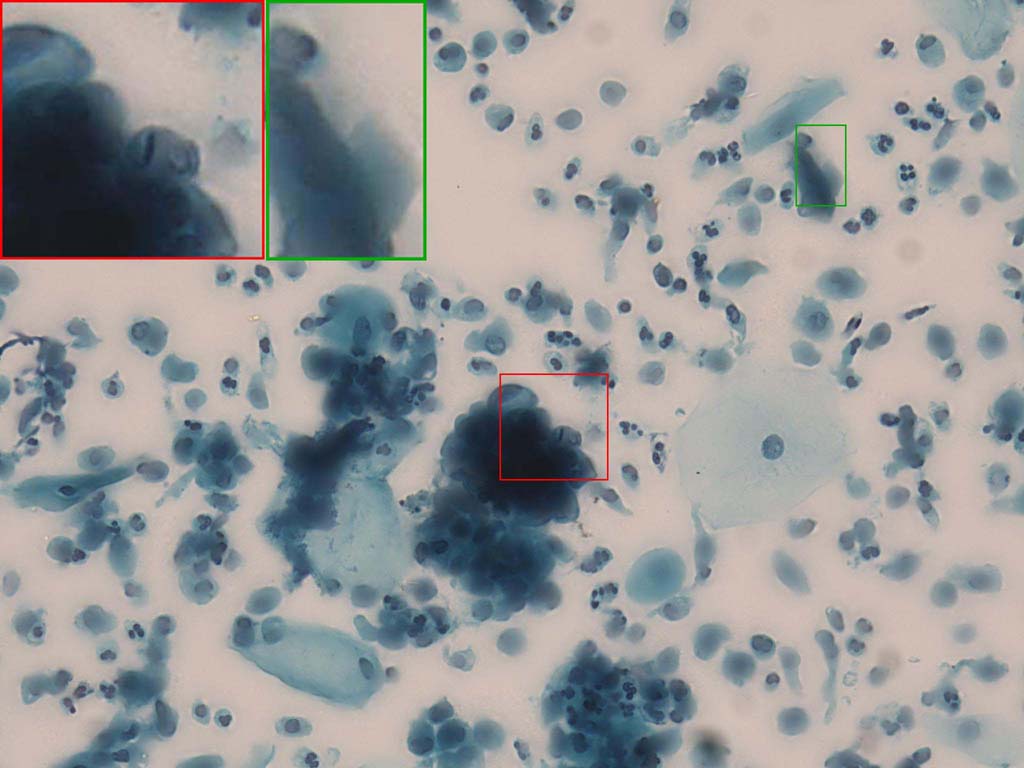

To demonstrate the effectiveness and efficiency of the proposed image fusion method , we conduct a set of comparative experiments on three image datasets. The first is composed by 8 pairs of multi-modal medical images and the second one contains 15 pairs of multi-focus gray or color natural images. These two datasets are often used in many related papers and some examples are shown in Figure 3(a) and Figure 3(b). The third one is a new multi-focus cervical cell image dataset collected by ourselves, which consists of 15 groups of color images and each group contains a series of multi-focus cervix cell images with size of or , etc. Some source examples are shown in Figure 3(c). Our source code implemented in C++ along with the new multi-focus cervical cell image dataset is available online.

Figure 9, Figure 10 and Figure 11 show the comparative fused results of the multi-focus cell images shown in Figure 3(c). For clarity, we also present a closeup view in the right-bottom of each sub-picture in Figure 9 and Figure 10. As shown in the close-up views of Figure 9, the fused images based on DSIFT, IM, MWGF and BF methods are extremely blurred in the boundary and fail to keep the details of cell nucleus. Furthermore, the DTCWT and NSCT based methods produce halo artifacts in the fused images, while GFF and CNN based methods fail to preserve the small cell nucleus. LP-SR based method nearly works fine which keeps the most of the details of the small size cells, but the integrity of the clustered large size cells is damaged. Fortunately, in our proposed method, the integrity of the clustered large size cells is preserved and most of the isolated small size cells are maintained from the original images, which demonstrates the best visual quality.

Similarly, as shown in the close-up views of Figure 10, the fused images from DSIFT, IM, MWGF and BF are blurred and lose some nucleus details, while the results from DTCWT, GFF, CNN and NSCT produce halo artifacts. LP-SR based method can keep details well but also produces halo artifacts and other noise. Our method can preserve the focused areas of different source images well without introducing any artifacts. For the example illustrated in Figure 11, the fused images generated by DSIFT, DTCWT, IM and NSCT all fail to preserve the focused areas of different source images and result in extremely blurred images. The GFF, CNN, MWGF and BF based method introduces a lot of color distortion of the nucleus regions and the obvious halo artifact. The result of LP-SR based method is close to the one of our method but introduces some odd color distortion. Again, our method produces fused image which can preserve the focused areas of different source images well without introducing any artifacts.